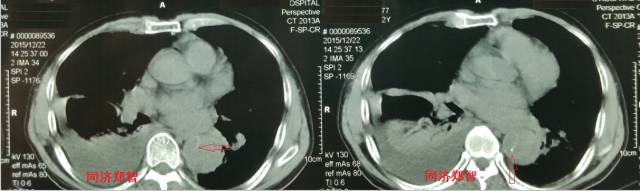

■ 病例四

腹部平扫CT提示腹主动脉增宽,CTA证实为腹主动脉局限性夹层(红箭头所示)